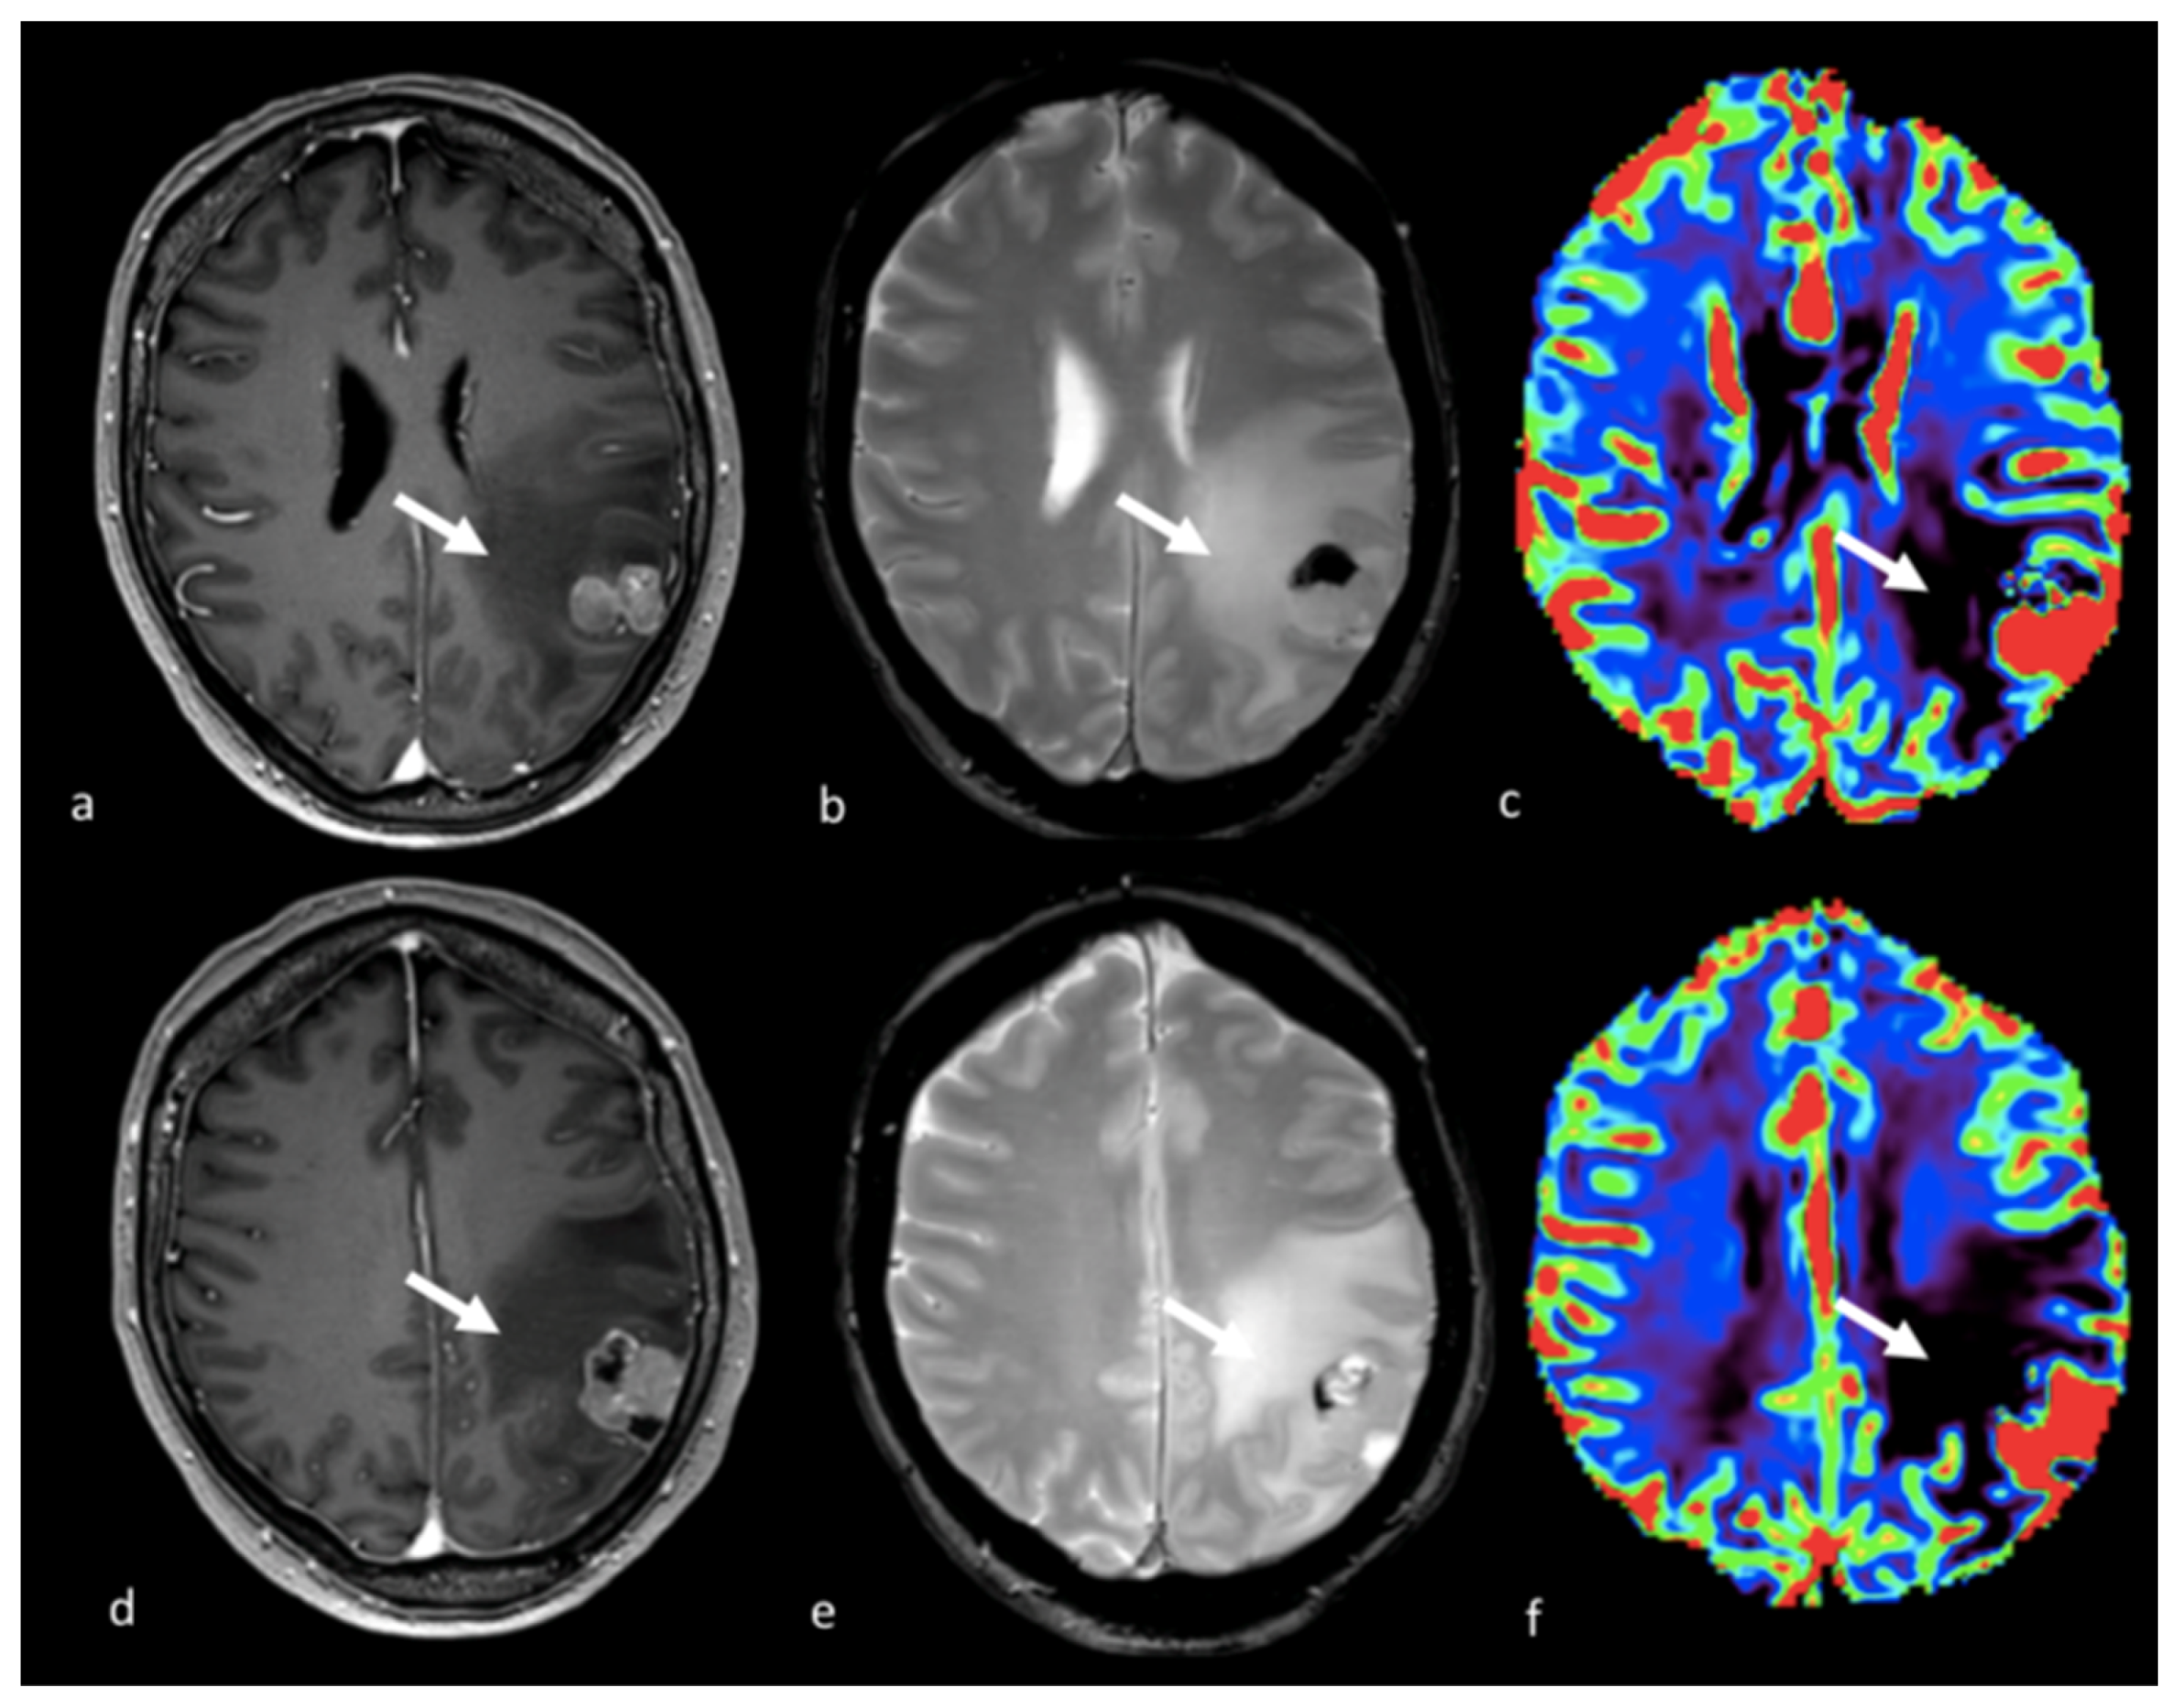

- Sunwoo, L.; Yun, T.J.; You, S.H.; Yoo, R.E.; Kang, K.M.; Choi, S.H.; Kim, J.H.; Sohn, C.H.; Park, S.W.; Jung, C.; et al. Differentiation of Glioblastoma from Brain Metastasis: Qualitative and Quantitative Analysis Using Arterial Spin Labeling MR Imaging. PLoS ONE 2016, 11, e0166662. [Google Scholar] [CrossRef] [PubMed]

- Lin, L.; Xue, Y.; Duan, Q.; Sun, B.; Lin, H.; Huang, X.; Chen, X. The role of cerebral blood flow gradient in peritumoral edema for differentiation of glioblastomas from solitary metastatic lesions. Oncotarget 2016, 7, 69051–69059. [Google Scholar] [CrossRef] [PubMed]